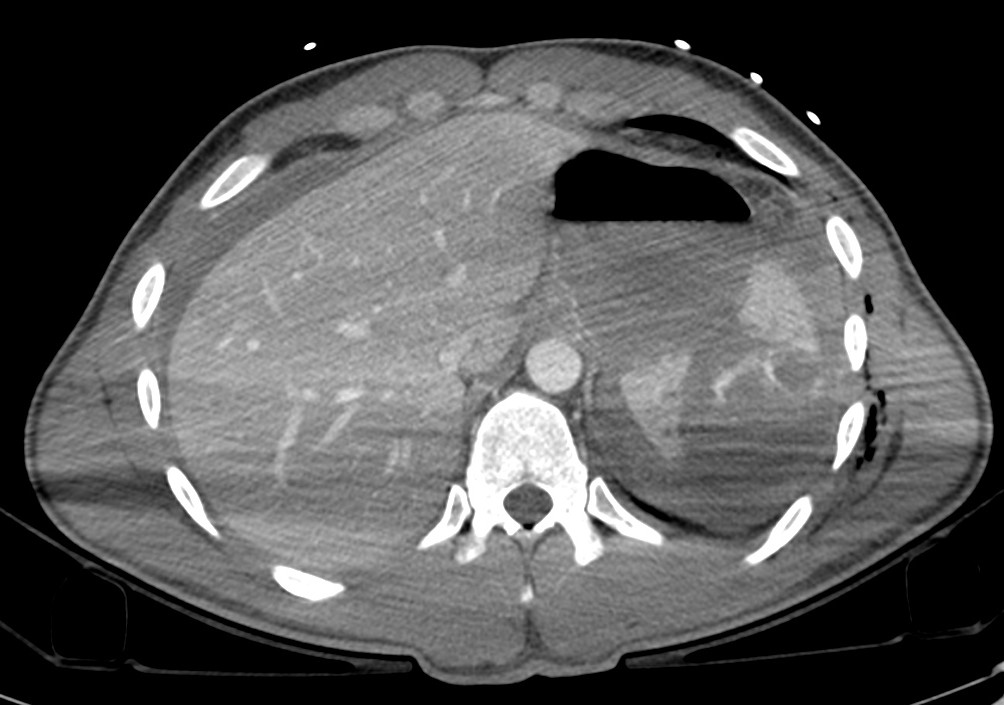

Varón jóven que acude a urgencias tras accidente de moto. Presenta dolor acusado en flanco izquierdo.

TA: 80 / 50 ; FC 110 lpm; Sat O2 93%.

Analítica: Discreta anemia.

Ante estos hallazgos, estamos ante un traumatismo esplénico grado III. Con la edad del paciente y los indicios de inestabilidad hemodinámica, se decidió tratamiento mediante embolización arterial.

- Laceración: líneas hipodensas e irregulares.

- Hematomas: áreas hipodensas focales en el interior del parénquima realzado.

- Hematomas subcapsulares: areas de baja densidad de morfología elíptica entre la cápsula esplénica y el parénquima realzado, la cual produce una marca o efecto de masa en el margen esplénico. El sangrado libre en el peritoneo no produce este efecto.

- Hemorragía activa: áreas de alta densidad (80 – 95 UH) por extravasación de material de contraste que aumenta con el tiempo. Es un indicador de fallo del tratamiento conservador.

- Hemoperitoneo: en posición supina, la sangre puede extenderse hacia pelvis menor. Antes, el volumen de hemoperitoneo se usaba como predictor de necesidad de cirugía en pacientes con traumatismo esplénico. Estudios recientes, demuestran el uso de tratamiento conservador en pacientes con grandes hemoperitoneos.